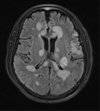

Metástases cerebrais

Arteriopatia idiopática progressiva da infância, não inflamatória, não aterosclerótica, descrita mais comumente no japão.